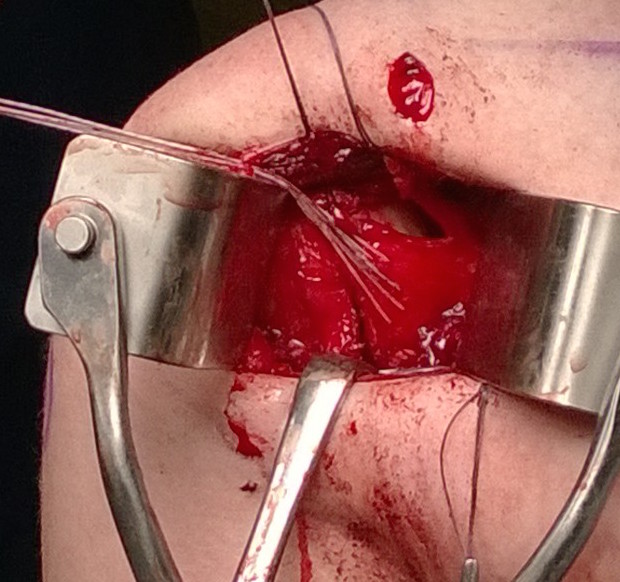

Open posterior capsular plication +/- allograft reconstruction +/- subscapularis shift / Putti-Platt

Technique

Open posterior capsular reconstruction with acellular dermal allograft PDF / video

Lateral Position

- vertical incision over glenohumeral joint

- elevate deltoid or split deltoid

- interval: between supraspinatus and infraspinatus

- interval: between infraspinaus and teres minor

- can detach infraspinatus tendon and elevate off capsule

- suprascapular nerve 1.5cm medial to glenoid

- axillary nerve below teres minor

- perform capsular plication / capsular shift

- +/- lateral advancement of infraspinatus

Open posterior approach in beach chair with detachment of deltoid

Infraspinatus tenotomy

Open posterior capsular plication in lateral position